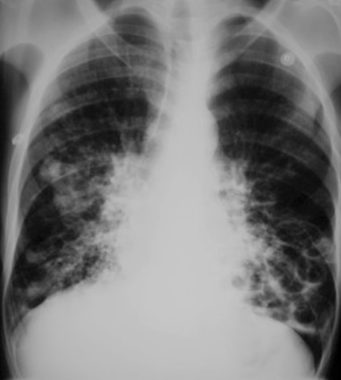

Rx toracică, incidență P-A

DESCRIERE:

pe tot teritoriul pulmonar, bilateral → opacități nodulare multiple de dimensiuni variabile, intensitate medie-mare, omogene, cu contur net

distribuție anarhică

blocuri adenopatice la niv. hilurilor pulmonare

DX: MTS pulmonare hematogene

DD:

hidatidoză - dimensiuni mai mari

bronhopneumonie - contur neregulat, neomogene, distribuție bazală